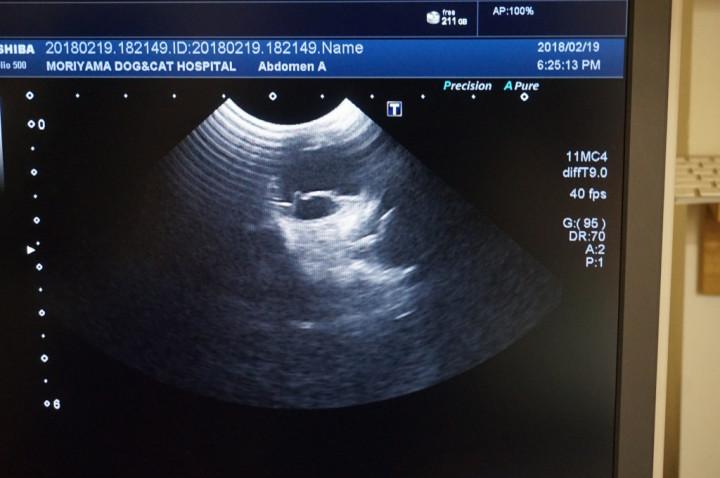

瞳孔検査は、目薬で瞳を開いて15分ほど経過したらエコーで眼底検査をします。

光には反応するけど、両目ともに網膜剥離の診断が出てしまった。

19日に必要な検査がなされていて、網膜が完全には剥がれてなくて、波を打ってるような状態、破れず膨らんでる状態だと説明を受けました。